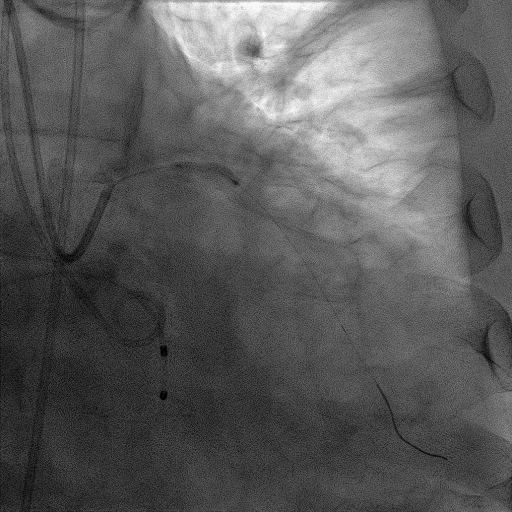

CAG:LAD近中段弥漫钙化,近段80%狭窄,中段90%狭窄,D190%狭窄,中间支近段90%狭窄,右冠近中段弥漫病变,最重狭窄50%。考虑患者胸痛症状可能为冠心病+AS共同作用,以及患者冠脉病变钙化严重,予以旋磨+PCI+TAVR一站式处理。

于中间支植入2.5*18mm支架

1.5mm旋磨头以16万RPM旋磨三次

3.0*15mm球囊后扩张

3.0*15mm球囊预处理LAD近段病变

复查冠脉造影结果满意